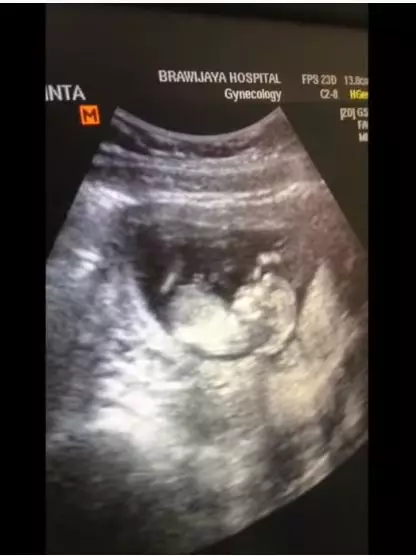

5. Momen Vebby memeriksa kandungan untuk ketiga kalinya. Selalu ingin melihat tumbuh kembang janin.

6. Dokter menjelaskan satu persatu organ tubuh si kecil di dalam gambar USG.